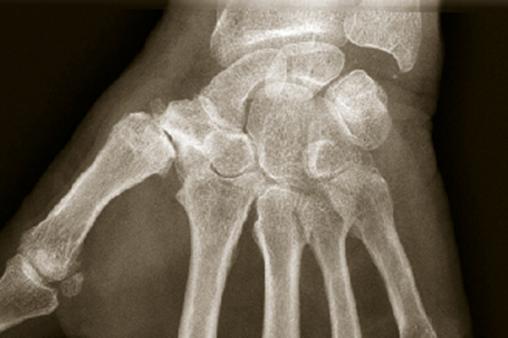

Rhizarthrose

Radiographie d'un arthrose du pouce